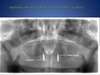

Prothèse complète amovible inférieure stabilisée sur 2 implants (Locator)

Complets haut et bas vissés sur 6 implants